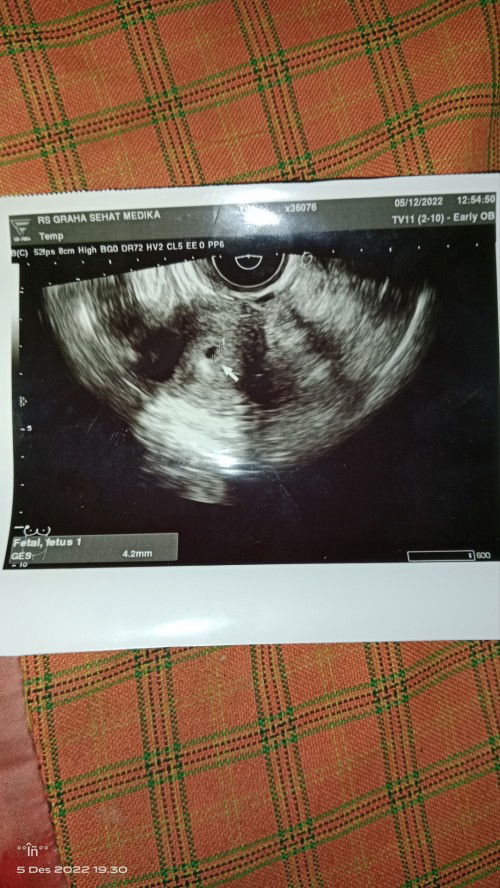

Hallo bun sekedar sharing ,ini hasil usg saya usia kehamilan 8 minggu,,udh ada janin dan detak jantungnya alkhamdulillah bun,,tapi wajar gak kalo buat makan/minum lidah terasa pahit??kalo buat bersin/batuk perut terasa nyeri kencang banget Adakah yang sama bun??#seriusnanya #bantusharing #ingintahu #firstmom #pleasehelp #firstbaby